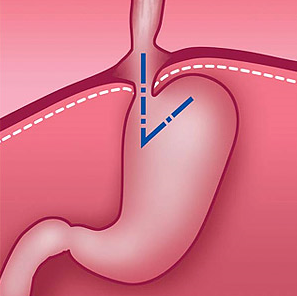

Нормальное положение желудка и угла Гиса (схема).

Под действием различных факторов связки, фиксирующие желудок и пищевод, растягиваются, соотношение между пищеводом и желудком изменяется. В результате часть желудка и пищевода, чаще при изменении положения тела, свободно перемещаются через расширенное отверстие диафрагмы в полость грудной клетки и возвращаются обратно.

При этом полностью сглаживается угол Гиса — в норме это острый угол, образованный при впадении пищевода в желудок. Это анатомическое образование препятствует обратному забросу пищи из желудка в пищевод. В результате изменения угла Гиса и нарушения функции нижнего сфинктера пищевода содержимое желудка или желчь свободно попадают в пищевод. Обладая агрессивными свойствами, содержимое действует на слизистую оболочку, в результате чего развивается воспалительный процесс в пищеводе — рефлюкс-эзофагит.